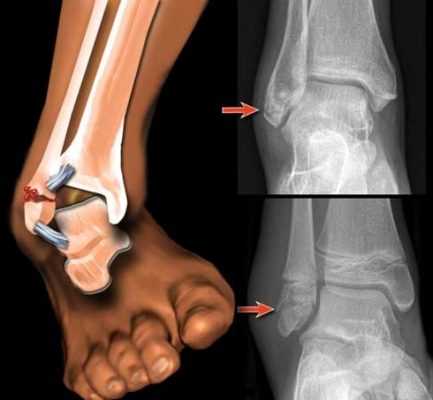

В результате потери костной ткани часто развиваются патологические переломы. Это нарушение целостности кости в области максимальной хрупкости.

Отличительной особенностью патологических переломов шейки бедра от простых считается то, что они возникают при незначительной силе травмирующего фактора.

Повреждение костей происходит при слабом ударе или падении с небольшой высоты. С подобной проблемой чаще сталкиваются люди пожилого и старческого возраста.

Симптомы патологического перелома шейки бедра:

- Сильные боли в паховой области.

- Укорочение больной ноги на несколько сантиметров (до 4 см).

- Поворот ноги наружу.